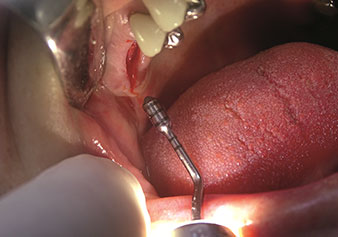

Situation following piezosurgical extraction

Fig. 2: Situation following piezosurgical extraction.

Photo: © Dr Torsten Conrad (Bingen am Rhein)